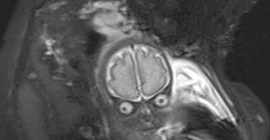

صُدم زوجان عندما ظهر طفلهما يشبه المخلوقات الفضائية، خلال جلسة فحص بالرنين المغناطيسي.

وأظهر مقطع فيديو الجنين داخل رحم والدته، والذي يشبه شخصية المخلوق الفضائي الغاضب من فيلم “هجوم المريخ”.

وقالت الأم لورا: إنها انفجرت ضحكًا هي وزوجها عندما اكتشفوا التشابه الغريب بين الجنين وأحد المخلوقات الفضائية في الفيلم، حيث ظهر بعيون بارزة وجمجمته يمكن رؤيتها بوضوح.